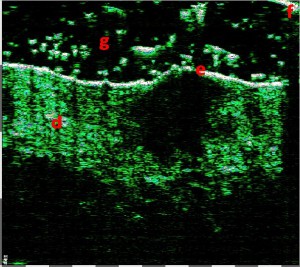

-Διαφοροποίηση μεταξύ υπερτροφικών και χηλοειδών ουλών

-Απλά διαγνωστικά κριτήρια κακοήθειας όγκου δέρματος

-Μελάνωμα

-Μέτρηση επιπέδων Breslow και Klark σε έμβιο οργανισμό (IN VIVO)

-Διαφοροποίηση τύπων βασικοκυτταρικού καρκινώματος